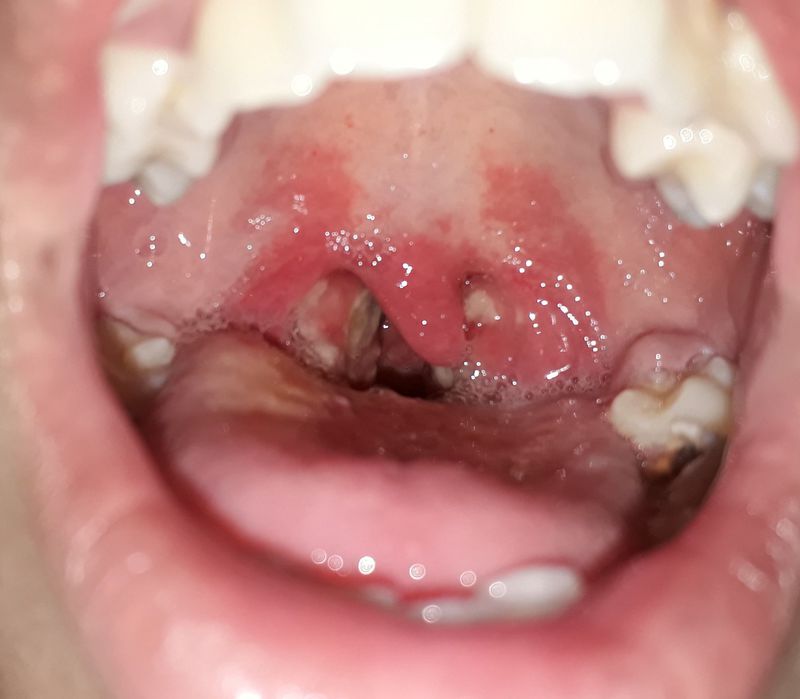

ENT case

Follicular Tonsillitis

Tonsillitis

Follicular